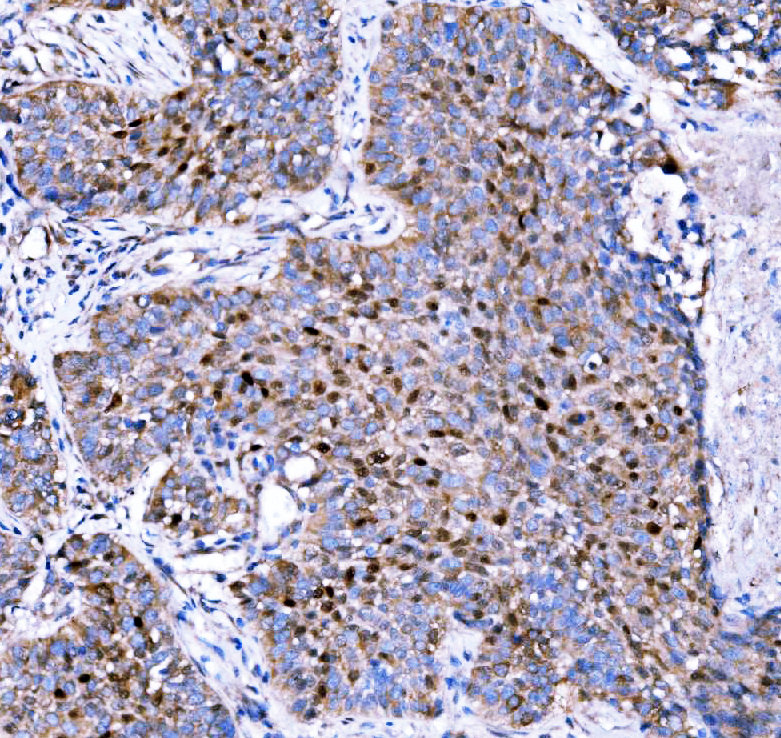

IHC analysis of p57Kip2/CDKN1C using anti-p57Kip2/CDKN1C antibody (A01244-2).

p57Kip2/CDKN1C was detected in a paraffin-embedded section of human lung cancer tissue. Biotinylated goat anti-rabbit IgG was used as secondary antibody. The tissue section was incubated with rabbit anti-p57Kip2/CDKN1C Antibody (A01244-2) at a dilution of 1:200 and developed using Strepavidin-Biotin-Complex (SABC) (Catalog # SA1022) with DAB (Catalog # AR1027) as the chromogen.